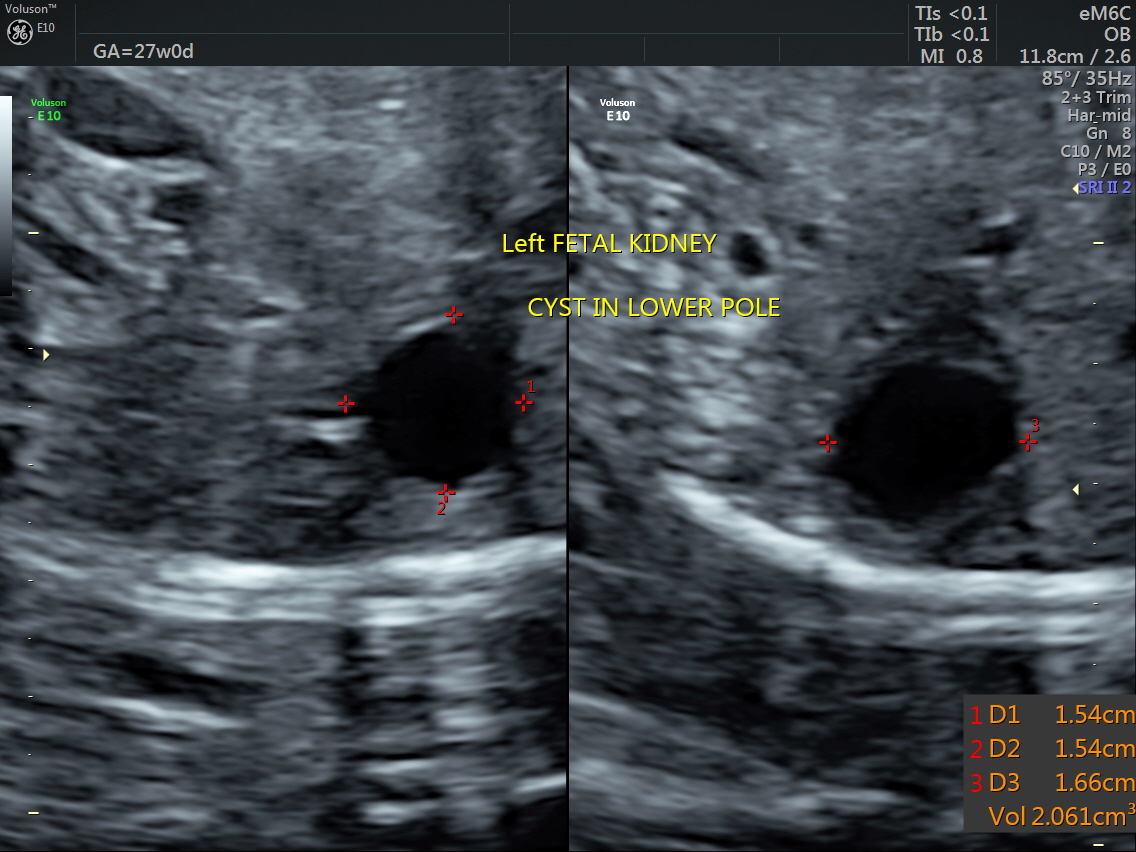

RT AORTIC ARCH_26 Published June 17, 2016 at 1136 × 852 in Rt aortic arch and aberrant left subclavian artery ← Previous Next →